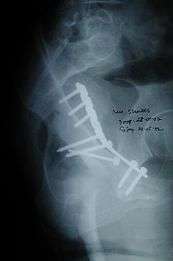

Surgical management

The surgical management requires high degree of training and well equipped centre. It should be carried out by experienced surgical team to get best results

Innominate bone is a flat bone with many curves. In most part the bone is thick enough and has broad surfaces that are amenable to primary fixation using lag screw(s) and to neutralize forces across the bone one needs to add plate(s) on the surface of the fractured fragments for it to heal without deformity.

Surgical approaches. Following are the common approaches;

- · Kocher Langenbeck approach for posterior injuries

- · Ili inguinal, Ilio femoral of modified stoppa’s approach for anterior or combined injuries

Implants : normally lag screws and reconstruction plates are preferred implants